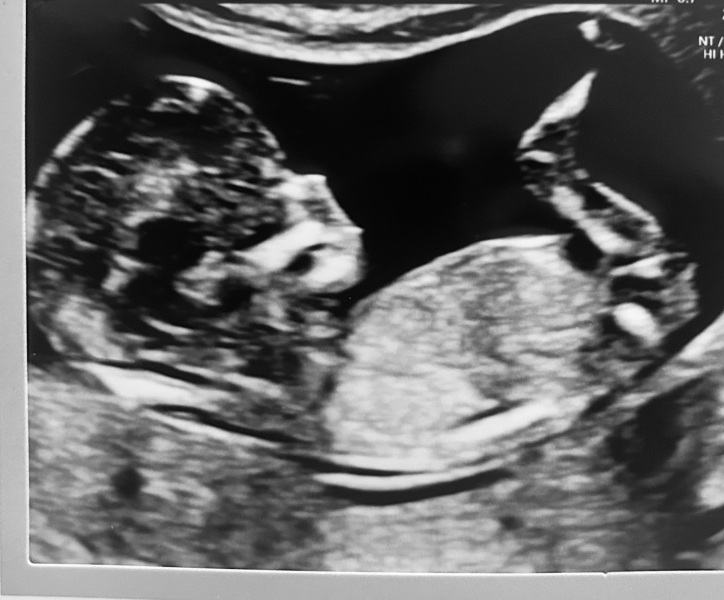

Butterfly2000 · 14/03/2024 19:50

I'm really having a baby! 😍🥹 12weeks and this is our first scan today

The tears started as soon as I saw baby. So excited

Butterfly2000 · 14/03/2024 19:51

I'm really having a baby! 😍🥹 12weeks and this is our first scan todayThe tears started as soon as I saw baby. So excited